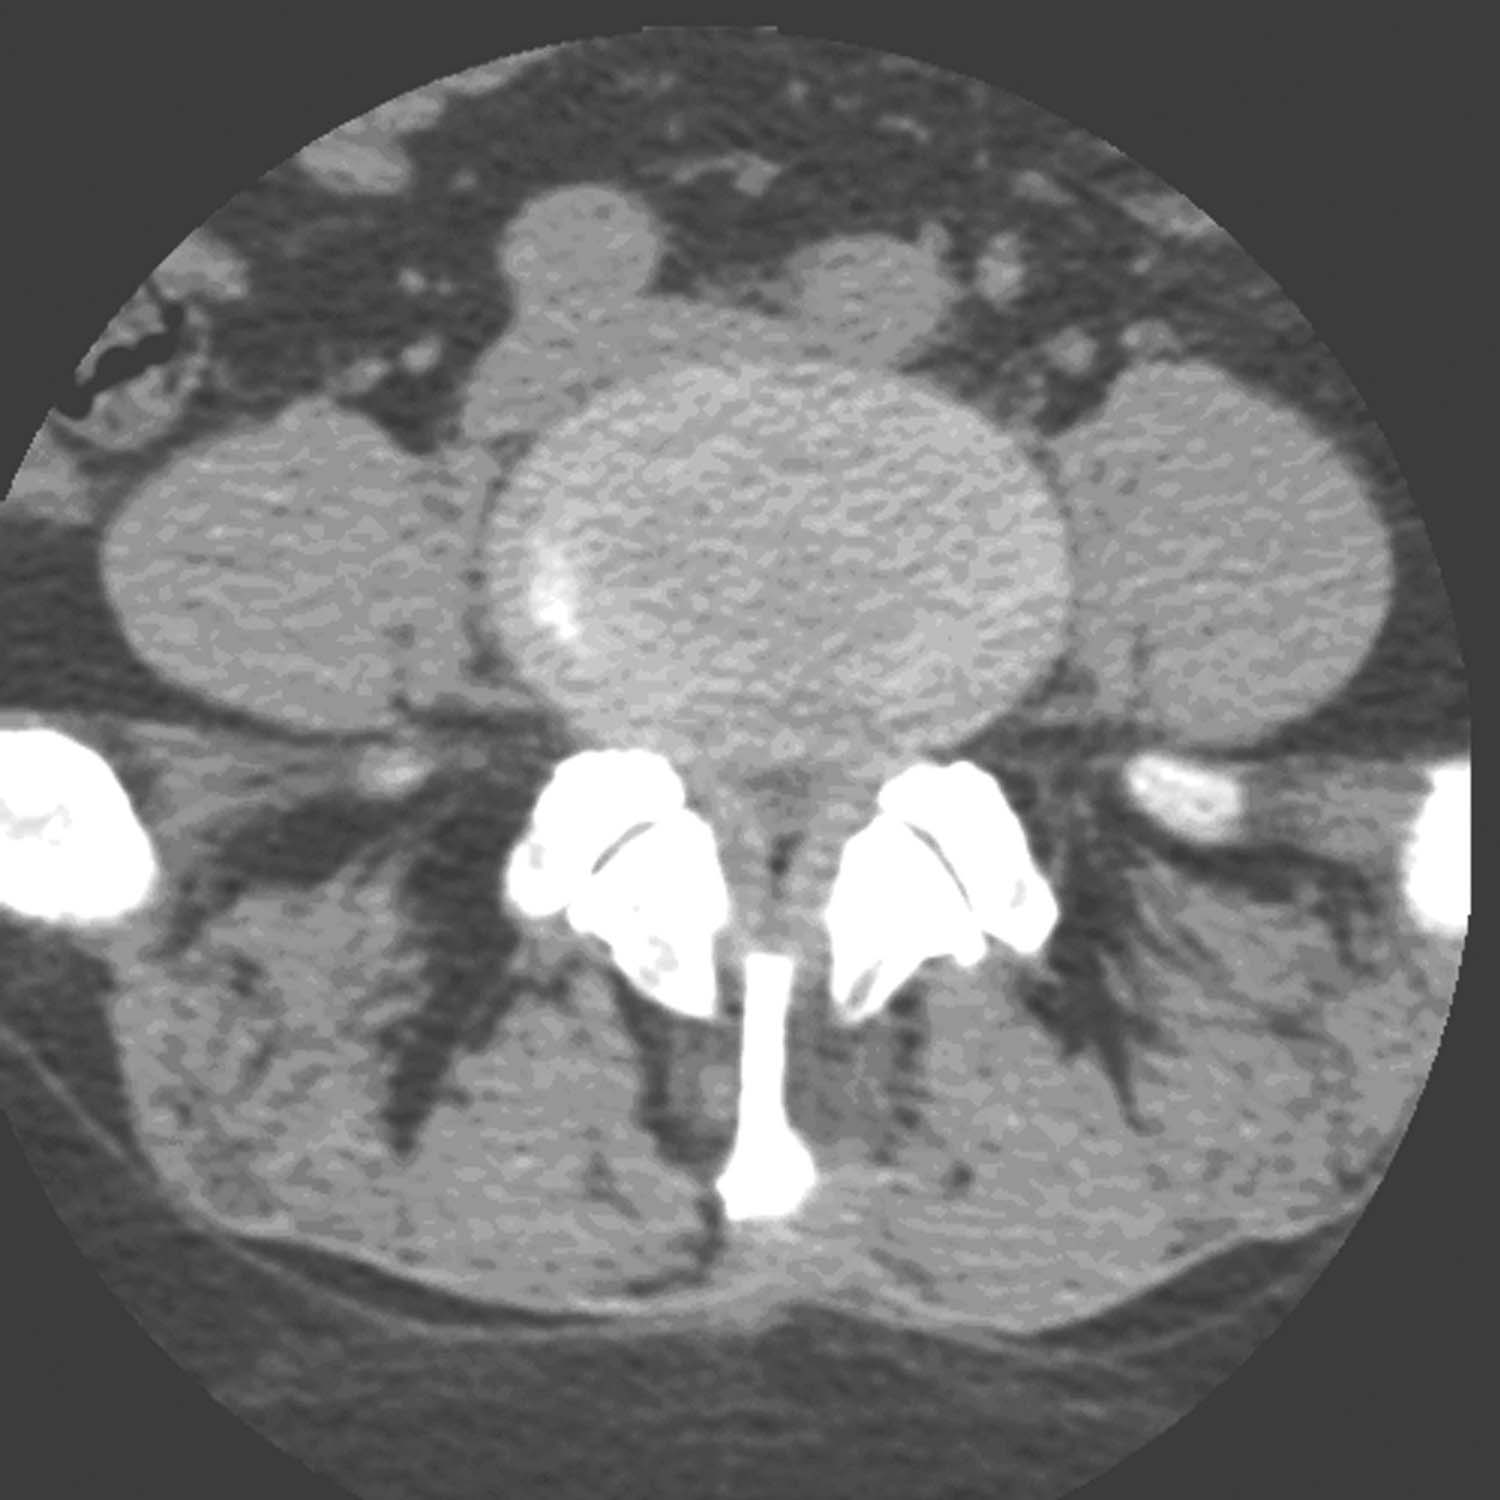

突出部位在椎管中央(图16-1-1),因此可以压迫脊髓双侧腹面而产生脊髓双侧受压症状。

图16-1-1 中央突出型